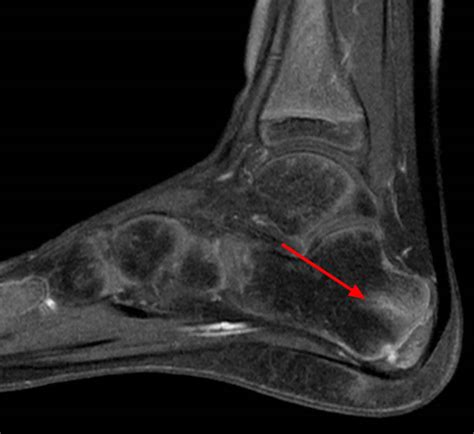

Diagnosing Sever's Disease

A healthcare professional will typically diagnose Sever's Disease based on a physical examination and a review of the child's medical history. During the examination, the doctor may:

• Press on the heel to check for tenderness

• Ask the child to stand on their toes to assess pain levels

• Order an X-ray or other imaging tests to rule out other potential causes of heel pain

It is important to note that Sever's Disease is a clinical diagnosis, meaning that it is based on the symptoms and physical examination findings rather than imaging results.